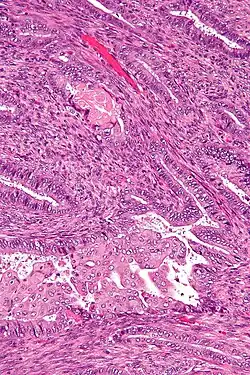

| Micrograph of an atypical polypoid adenomyoma. H&E stain. | |

APAs are characterized by glands with abnormal shapes that: (1) often have squamous metaplasia, and (2) are surrounded by benign smooth muscle.[1] Nuclear atypia, if present, is mild.

The microscopic differential diagnosis includes endometrial carcinoma and endocervical adenocarcinoma.